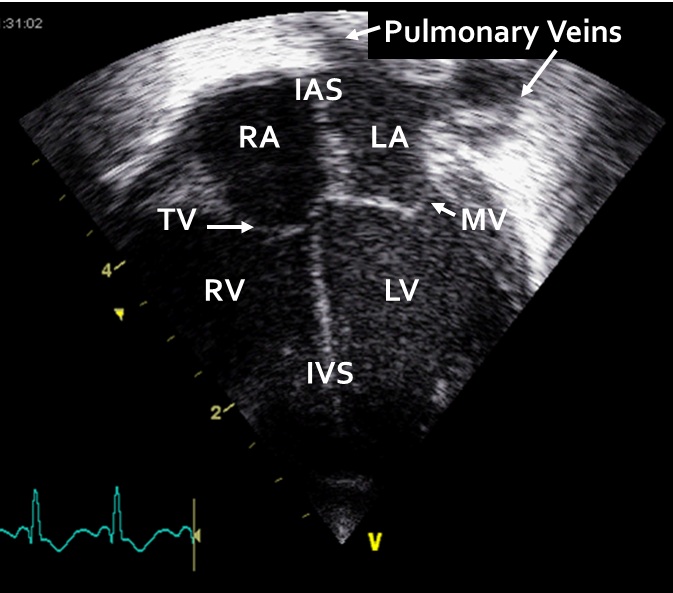

The Doppler loops demonstrate the assessment of the mitral valve, and the tricuspid valve.

Diastolic filling is influenced by the compliance of the ventricular wall. In adults and older children trans-mitral flow occurs in two phases; an early phase of passive flow during which the majority of the filling occurs and a late atrial contraction phase during which the remaining third of the venous return to the ventricle is delivered. In patients with diastolic dysfunction, the majority of filling occurs during the atrial phase as the stiff ventricular wall prevents passive early flow across the mitral valve. The immature fetal and preterm myocardium is characterized by impaired diastolic function. Pulsed wave Doppler can be used to examine this biphasic pattern of the RV and LV inflows. First phase is the early wave (E wave) and is a result of passive blood flow across the atria-ventricular valves in early diastole. The second phase is the atrial contraction wave (A wave) and is a result of atrial contraction at the end of diastole.

The four chambers are seen in this view. Two pulmonary veins are seen draining into the LA.